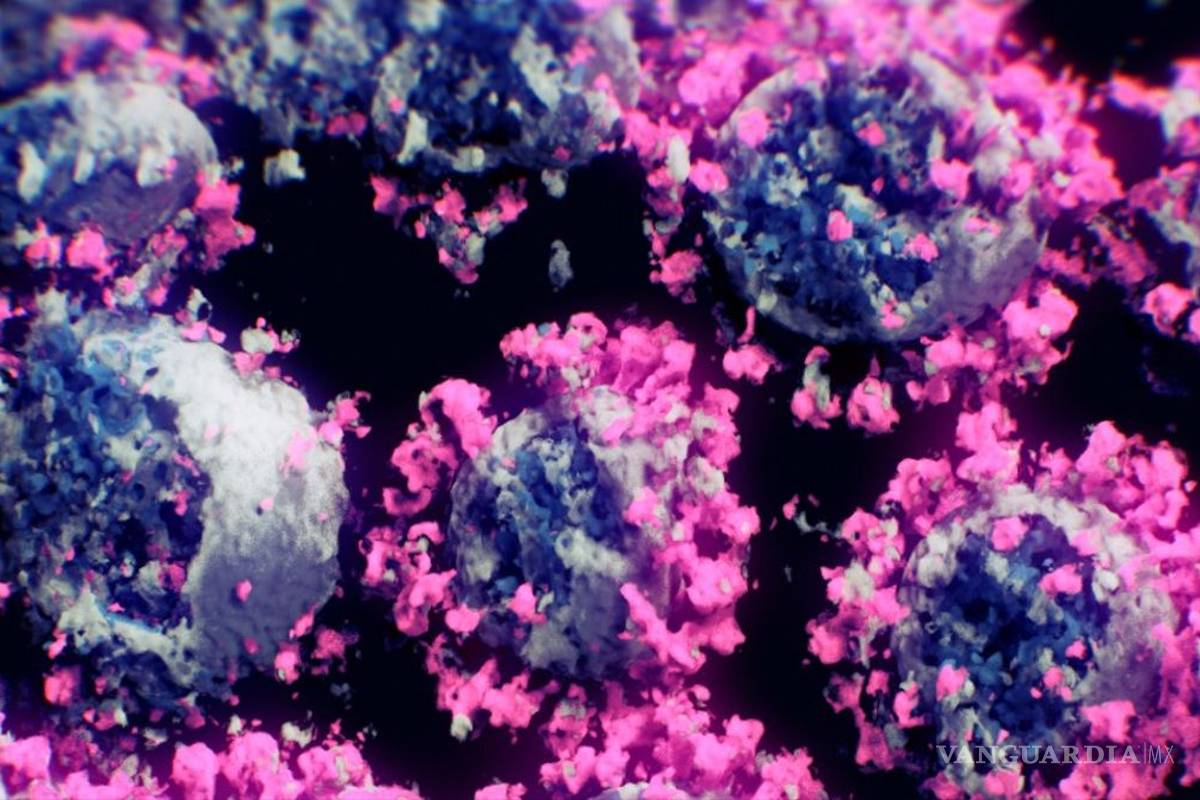

Recientemente un estudio reveló que el coronavirus puede alojarse y permanecer incluso después de la infección en el cerebro.

Mukesh Kumar, investigador de la Universidad Estatal de Georgia, quien encabezó el estudio, explicó que la prueba con ratones reveló que el covid-19 puede estar oculto, lo que puede provocar preocupantes recaídas de salud y que incluso pueden provocar la muerte.

“El cerebro es una de las regiones donde al virus le gusta esconderse", indicó el especialista. La investigación -publicada en Viruses- informó que la infección de los ratones de SARS-CoV-2 se dio mediante conductos nasales, lo que provocó enfermedades graves.

El estudio detalló que el coronavirus se encontró en el cerebro de los ratones a un nivel mil veces superior que en cualquier otra parte del cuerpo. Además de que pese a que la carga se diera de forma más baja, el virus podría permanecer intacto en su escondite.